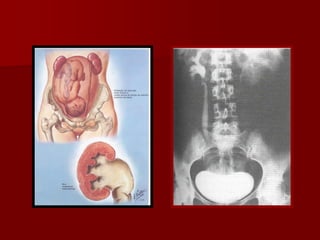

Alterações morfológicas das

vias urinárias

Dilatação da pelve renal e ureteres

Causa hidroureter fisiológico da gravidez

Mais comum no lado direito.

Dilatação da pelve renal na gestação e

puerpério